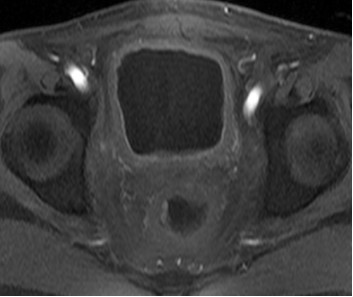

患者男性,63岁。诊断:直肠癌术后Ⅳ期,膀胱、盆腹腔及骨多发转移。患者2013年3月确诊后,行放化疗,后吃中药治疗,2015年12月病情恶化。2016年1月,盆腔MRI检查提示直肠癌侵及膀胱及周围组织,伴骶前转移及骶骨转移。2016年3月,CT检查提示直肠占位病变伴膀胱、前列腺、部分骶椎输尿管受侵,右侧大网膜强化结节,转移不除外,肠系膜及腹膜后淋巴结增大。肠镜检查提示肛管见菜花样肿物,肛管狭窄。化疗一疗程后,患者不能耐受而终止。为寻求下一步治疗方案,患者找到全球肿瘤医生网A45专家,经过中美癌症专家综合会诊,制定A45治疗方案。

患者于2016年6月开始A45治疗,一个疗程后复查,膀胱及直肠病灶明显缩小,肛周复发灶较前缩小,血尿症状消失,疼痛症状消失,其他症状显著缓解。